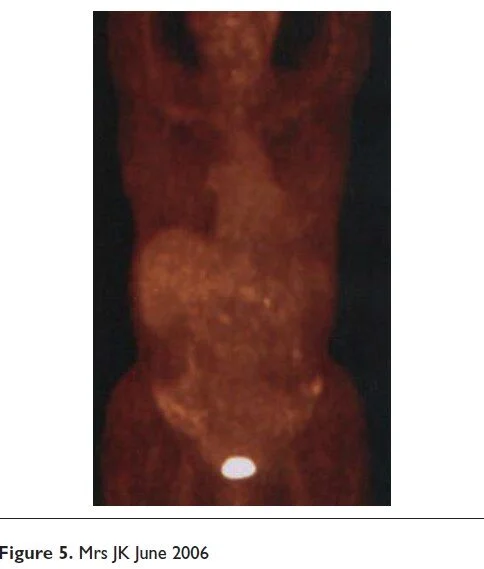

Le second patient, JK, présentant les mêmes symptômes cliniques et ayant suivit le même protocole, son PET scan après 5 mois montrait que la maladie n’était plus visible.

ALA Mr JK juin 2006.jpg